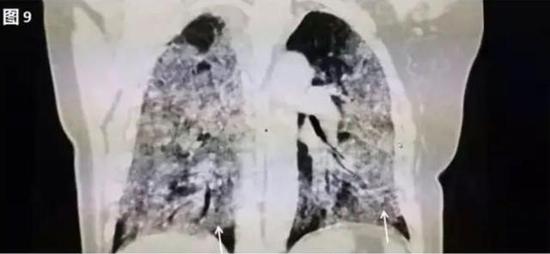

若病毒大量复制,或者患者免疫功能较弱时,会发展为危重症。此时病毒会攻击多个肺叶,肺泡损伤弥漫,病变范围扩大、融合,造成双肺实变,即从CT上看,患者的肺部呈一大片的白色状,医学上称之为“白肺”。这种情况会严重影响肺换气,患者需要持续吸氧。

▲白肺(图片来自网络)

按照国家卫健委发布的新型冠状病毒肺炎试行第六版诊疗方案之中的临床分型,新冠肺炎分为轻型、普通型、重型及危重型。在患者的肺部CT中,轻型者没有比较明显的肺炎改变;普通型者以肺部出现局限性斑片状或很多节段性片状“病灶”为主(图②);重型者双肺可出现较多的白色小斑片“病灶”,部分融合成大片状“病灶”(图③);危重型者会有“白肺”表现(图④)。

▲从上到下依次为普通型、重型及危重型新冠肺炎患者的肺部CT表现(图片来自网络)